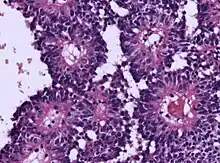

| Micrograph of an astroblastoma showing the characteristic nuclear pervivascular pseudorosette. H&E stain. | |